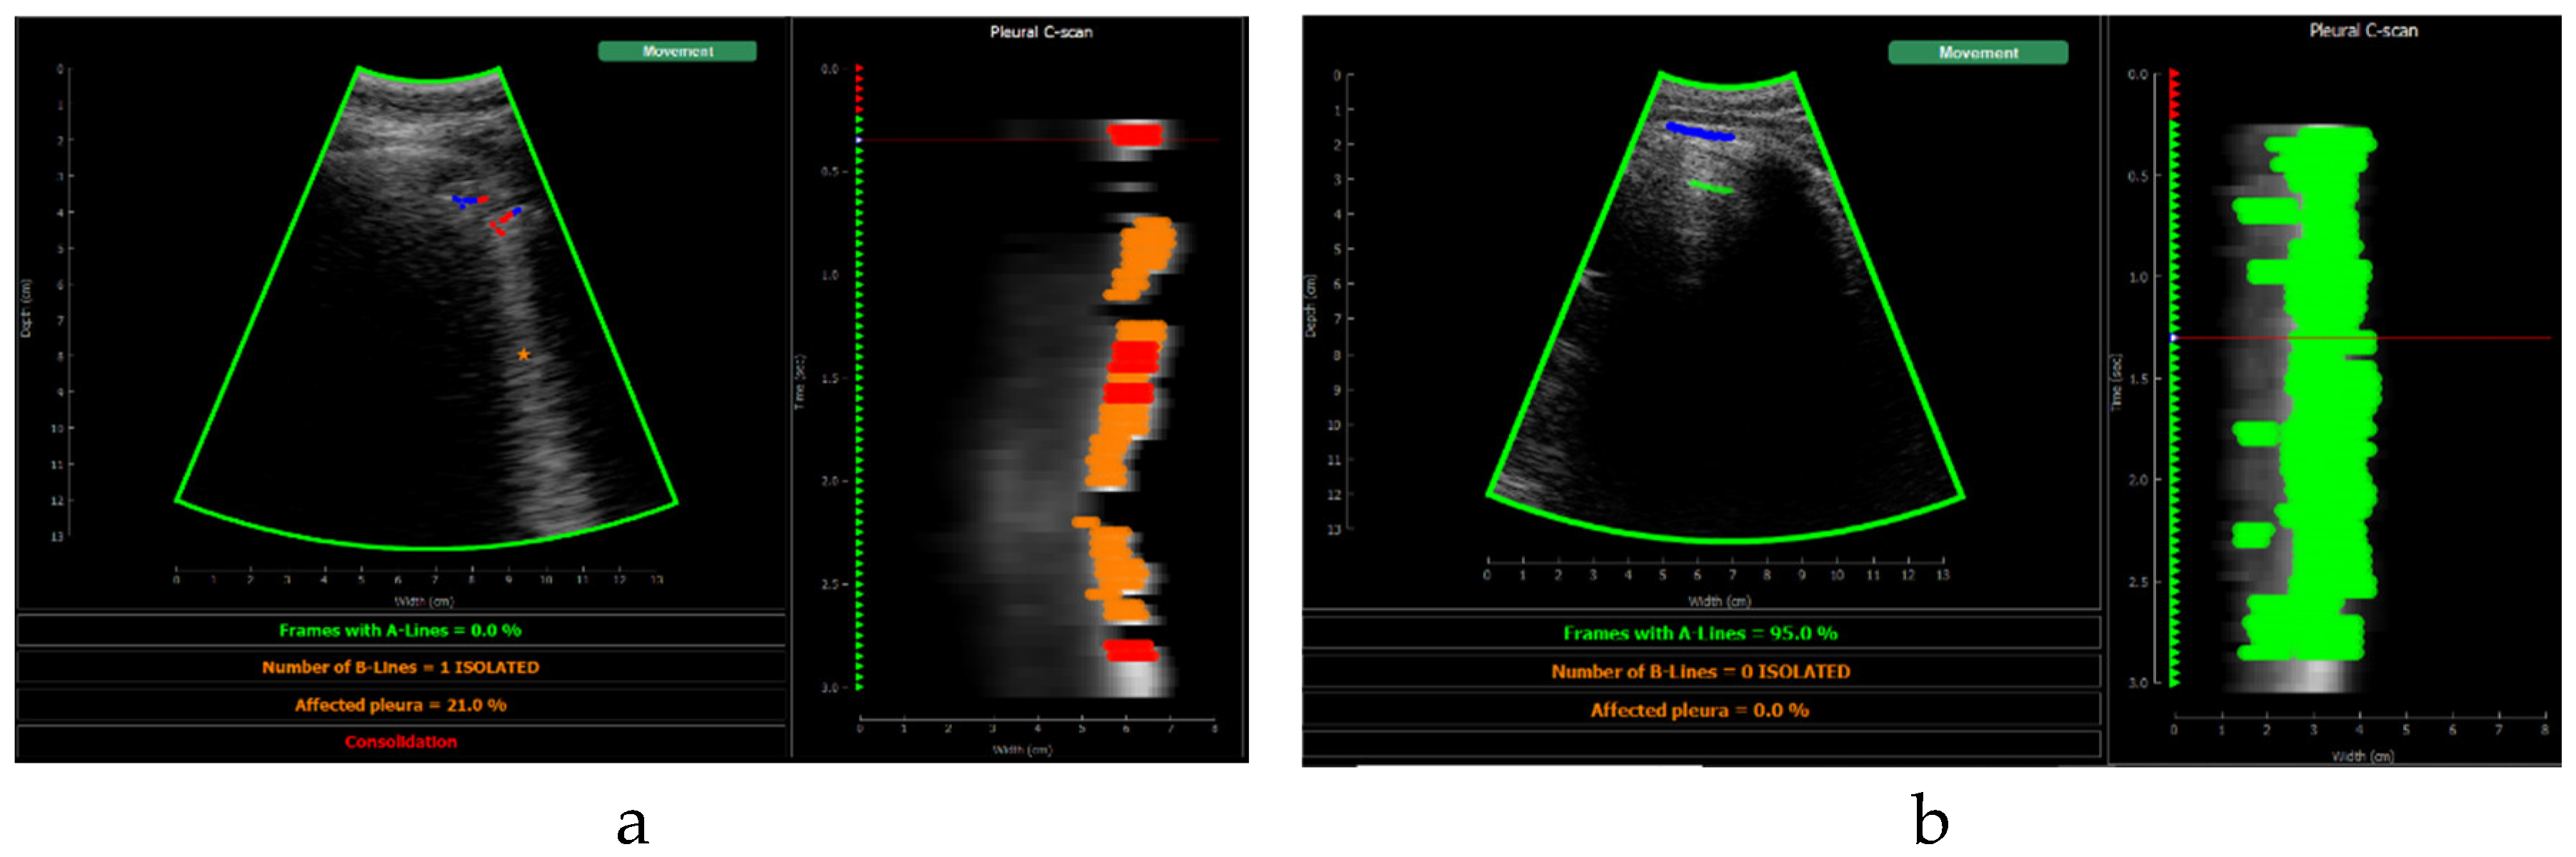

Figure 10 shows the screen shown to the user. On the left, the acquired sector-scan images are shown in real-time, with several overlays coming from the processing algorithm. When the image is valid for being evaluated, the contour of the image turns green, and so the label “movement” on the upper right corner. If the image fails to pass any of this criterion, the contour line turns red, and so the labels that triggered the event. Therefore, the physician can freely move the probe on the patient chest until theses indications turn green, and then hold probe steady to acquire a video of 3 seconds that will be saved for each of the 12 regions to be examined according to the protocol.

This image also overlays, in real-time, the findings of the neural network. The pleura is marked with blue points, A-Lines with green points, B-Lines with orange points and consolidations with red points. Furthermore, a series of statistics and messages are shown in the lower part of this image: The percentage of frames with A-Lines in the last 6 seconds, the number of isolated B-Lines, calculated as the sub-regions with an average 6dB drop in the angular direction within the region where B-Lines were detected, the percentage of the affected pleura calculated as the number of scan lines affected by B-Lines over the total number of scan lines where the pleura was detected, and a label in red indicating that a consolidation when present.

Figure 13. Application visualization sample: a)B-lines (orange) and consolidation (red) detection; b)normal lung with A-lines(green); c) probe movement detected; d) B line (orange) and A-line (green) deteccion on a Lung phantom. On the right of each image the C-scan image is shown.